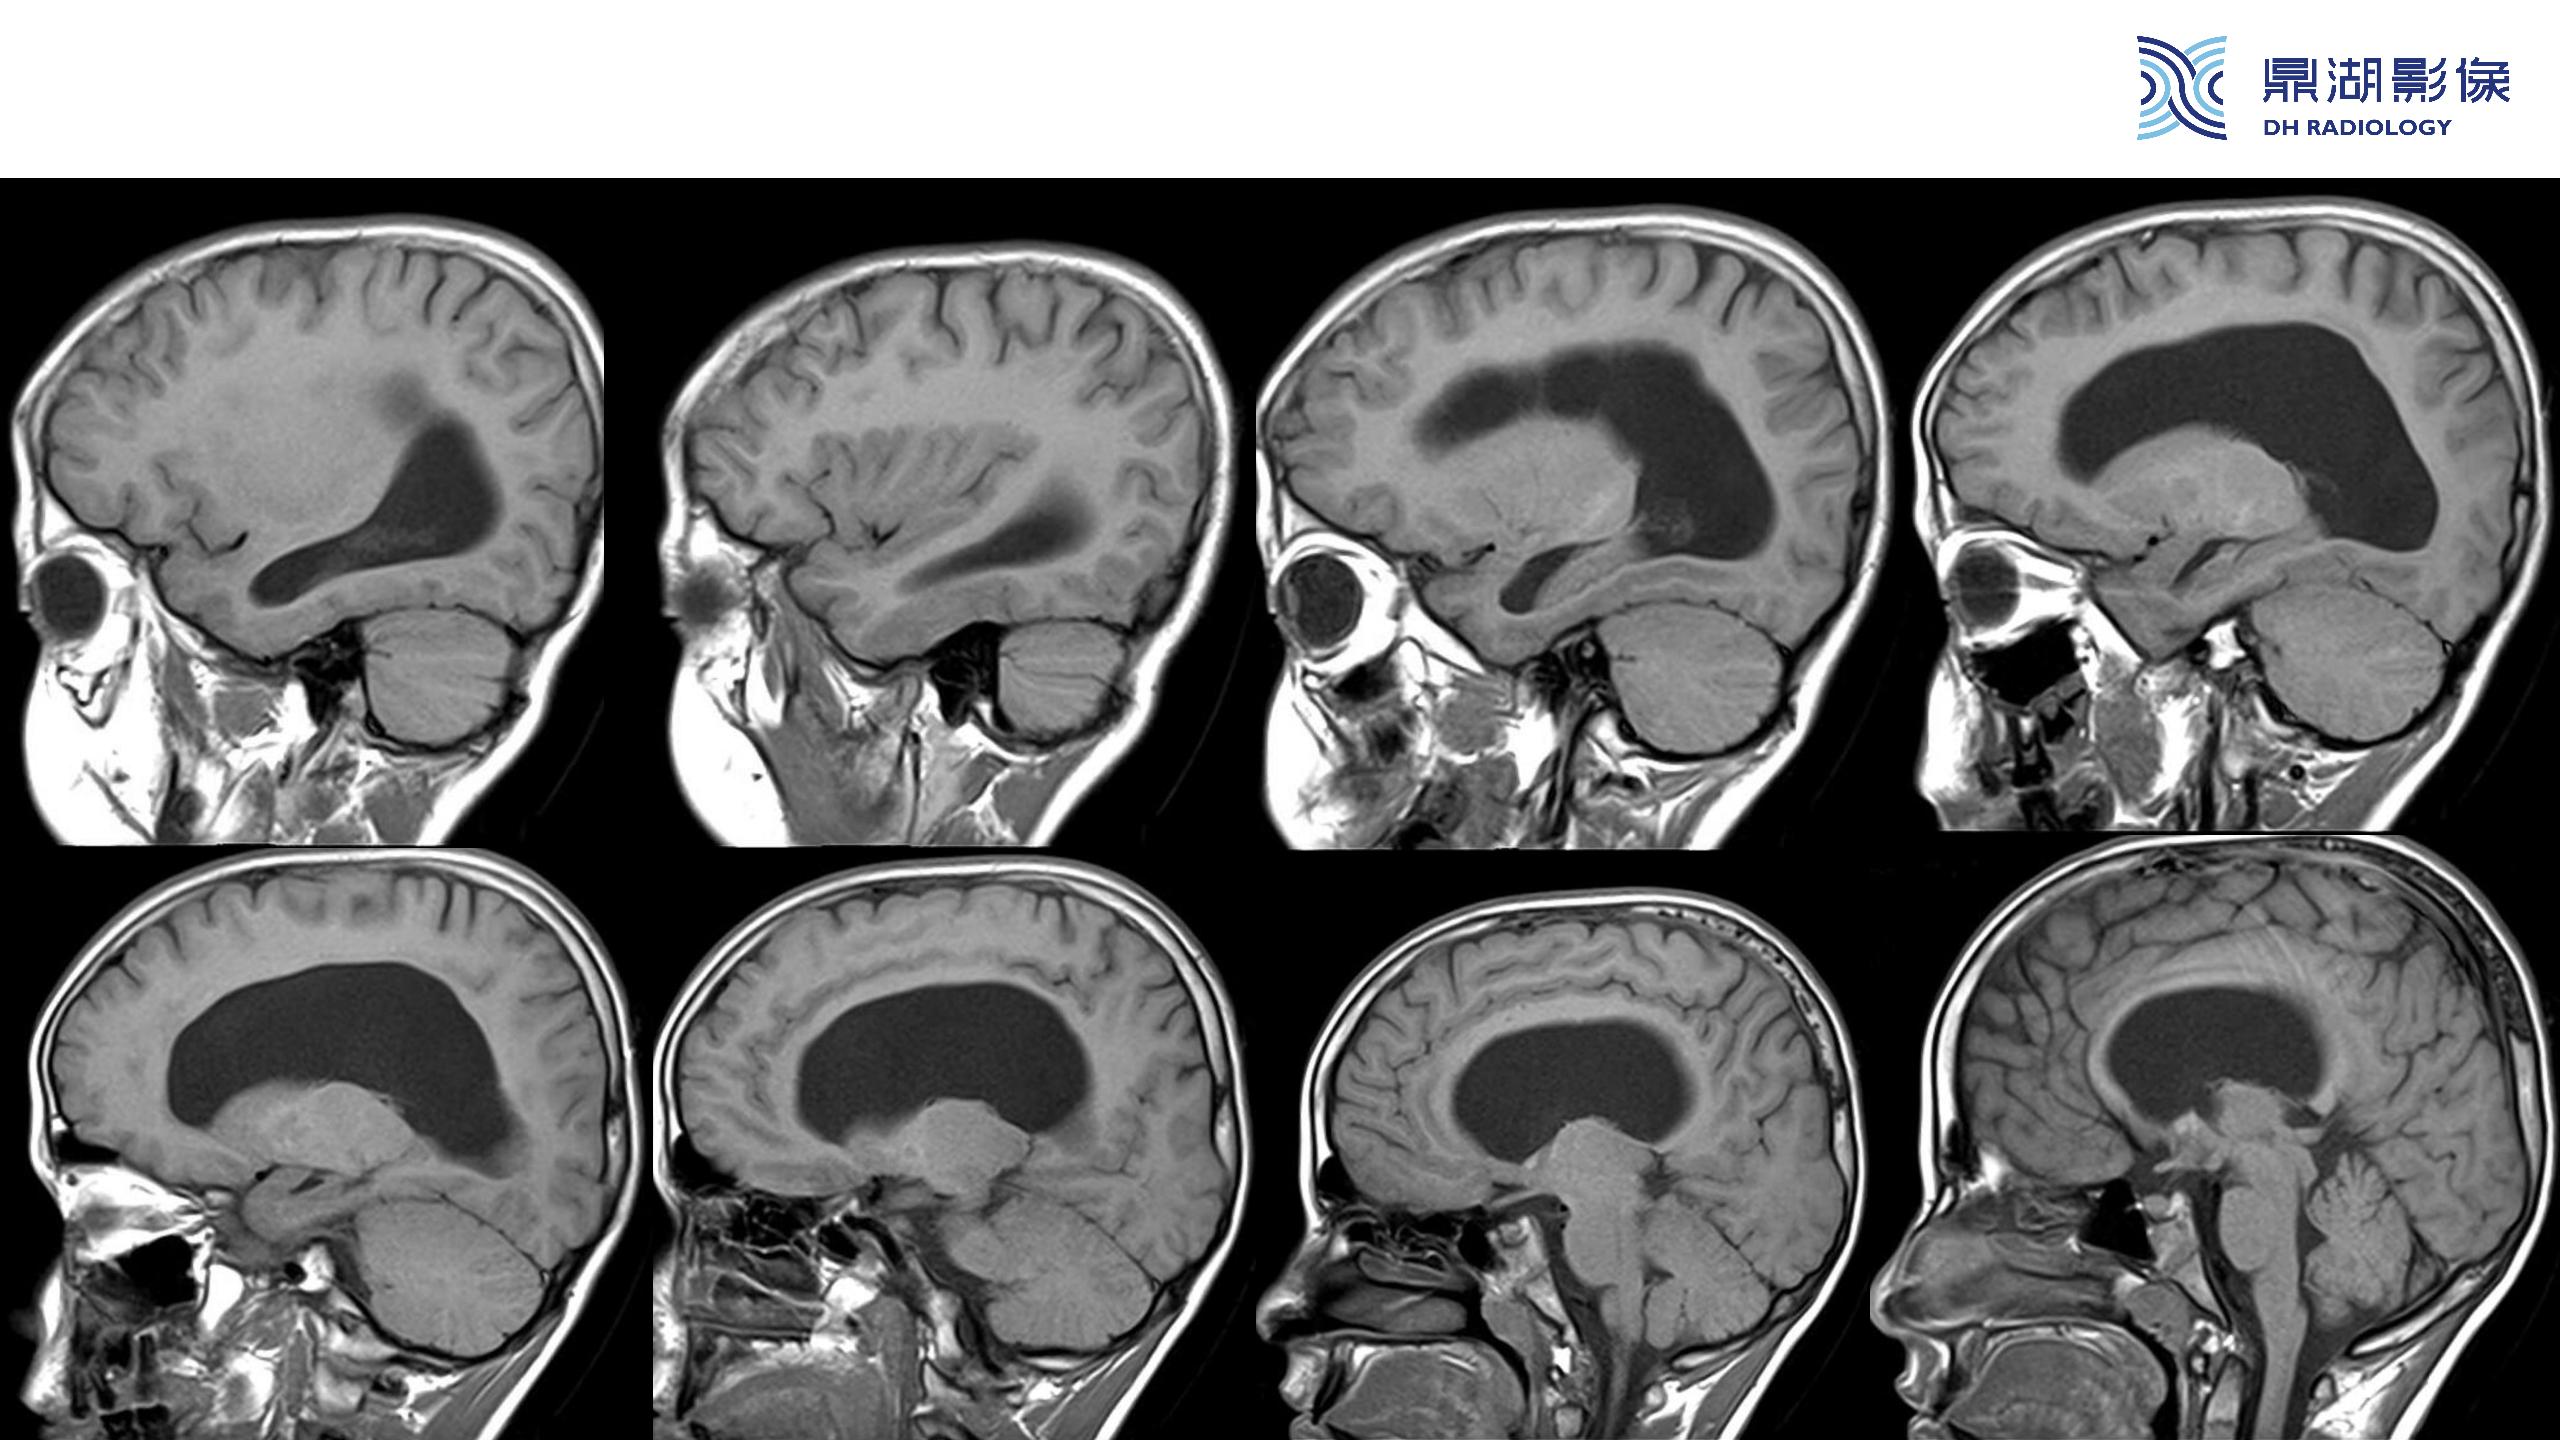

裂隙脑室综合征 (slit ventricle syndrome,SVS)-鼎湖社群读片病例